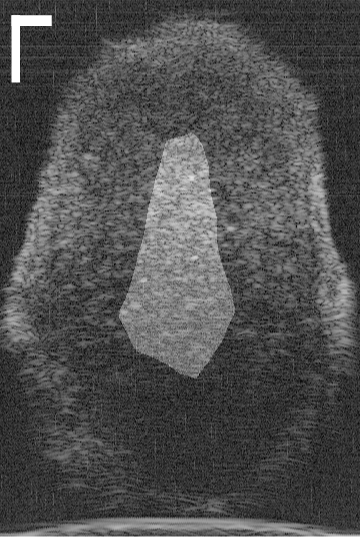

Figure 1(a) shows a representative HFU image of a human LN immersed in a phosphate-buffered saline (PBS) bath. Two different LN tissue types are visible: LNP (inside) and fat (surrounding). In order to perform QUS processing successfully, a 3D segmentation method is required to restrict QUS processing to LNP and to correct accurately for ultrasound attenuation [2]. Furthermore, accurate segmentation can provide detailed LNP shape information, which can be used to produce additional bio-markers of cancer.

III-A 3D HFU Data Acquisition

LN dissection, histological preparation and HFU data acquisition protocols were previously described in detail [2]. Briefly, LNs were dissected from patients with histologically-proven cancers at the Kuakini Medical Center (KMC) in Honolulu, HI. Individual, freshly dissected LNs were placed in a PBS solution at room temperature and scanned. Radiofrequency (RF) signals were acquired using a single-element transducer with a 12.2 mm focal length, an f-number of 2, and a center frequency of 25.6 MHz. The RF echo signals were digitized at 400 MS/s using an 8-bit A/D board. 3D HFU data were acquired from each LN by scanning adjacent planes with a uniform plane and A-line spacing of 25 μ𝜇\mum. The present segmentation study was carried out using a representative database of 3D HFU envelope data from 115 LNs (19 metastatic and 96 cancer-free LNs) from 67 colorectal-cancer patients. The Institutional Review Boards (IRBs) of the University of Hawaii and the KMC approved the participation of human subjects in the study. All participants were recruited at KMC and gave written informed consent as required by the IRBs.